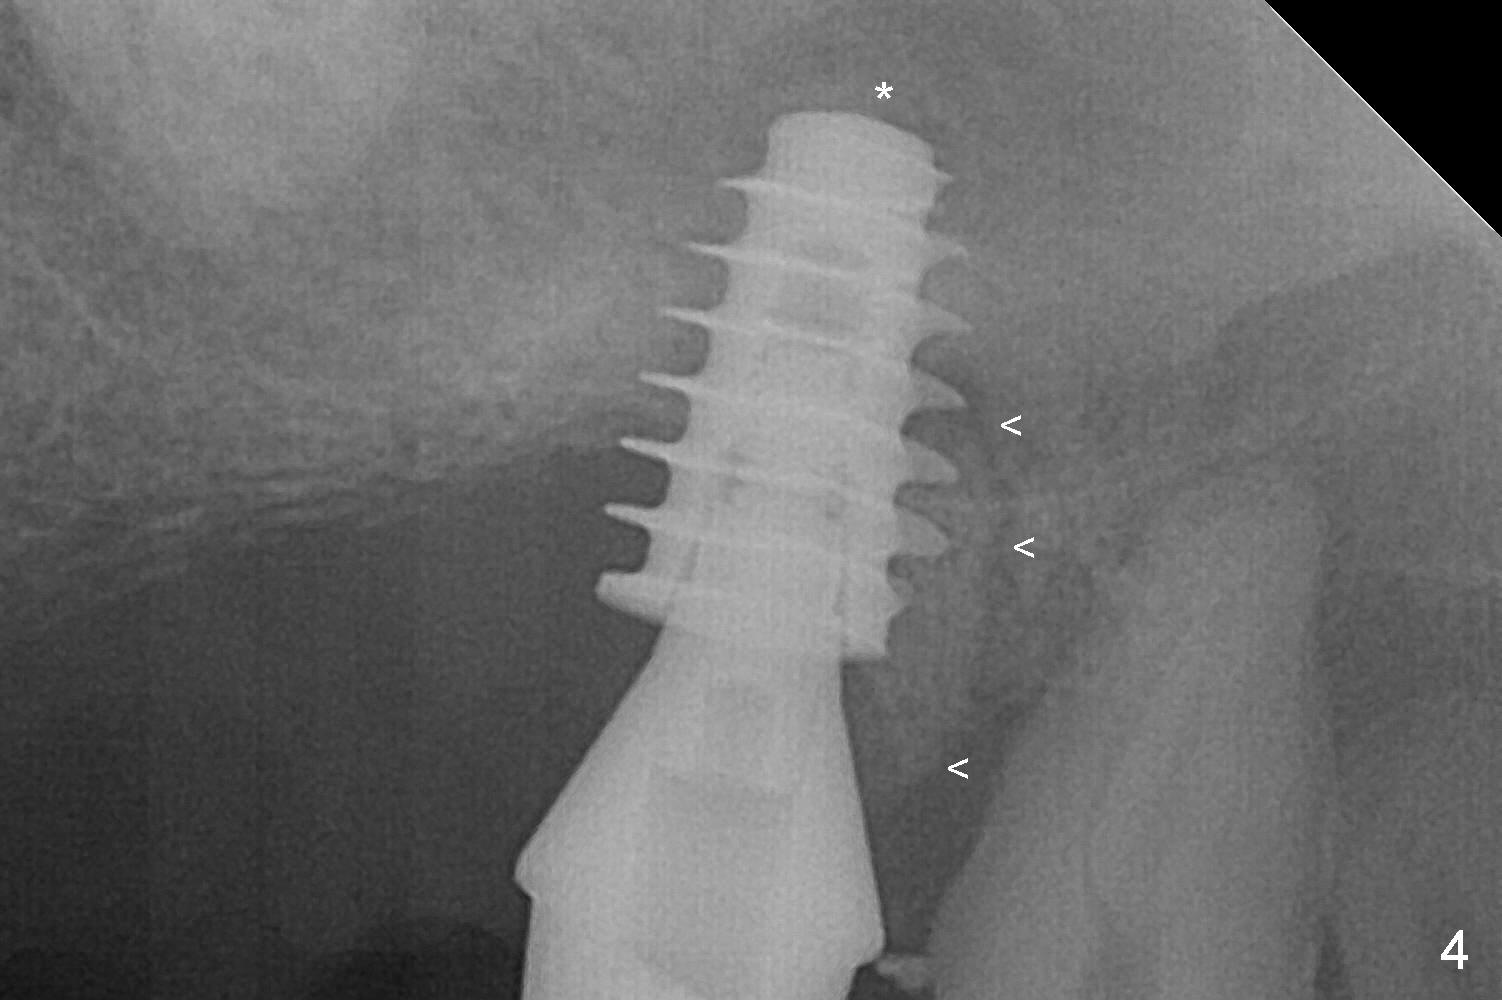

The posterior abutment of the 5-unit FPD, #15 is loose with the buccal roots extruded outside the sockets. The palatal socket is the appropriate site of immediate implant with the presence of the buccomesio-palatal walls, although short. The thinnest portion of the palatal socket is 1.6 mm (Fig.6 CBCT coronal section through the palatal root (P)). Magic Sinus Lifter cannot break through the sinus floor. UF drills are used to create osteotomy and sinus lift until 4.3 mm. A 5 mm tap drill is inserted without stability (Fig.1). A 5.5x9 mm IBS dummy implant achieves insertion torque of 10 Ncm, although it looks smaller (Fig.2) than the tap in Fig.1. After placement of PRF membrane and bone graft (allograft, autogenous bone and Osteogen, Fig.3 *), a 6x9 mm IBS implant is placed with insertion torque of 30 Ncm. It appears that the fins of the implant slice into the bone at high magnification for engagement. Following further placement of the implant, bone graft is packed into the distal portion of the socket (Fig.4 <). The thin fins extends into mesial and distal thicker bone (Fig.5 (CBCT sagittal view) *).